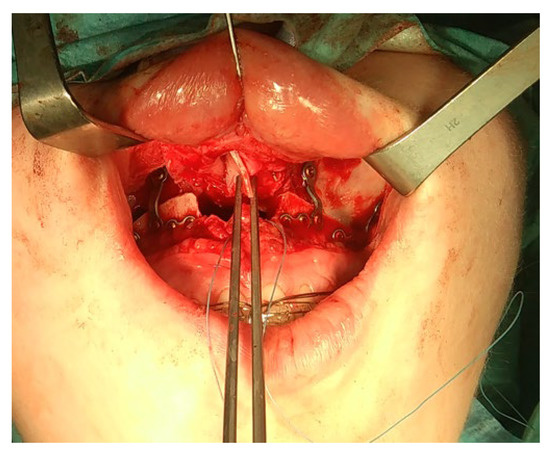

- A condylectomy with BSSO and Lefort I simultaneously was described by Wolford in 2002; however, some authors report operated TMJ joint instability, which might be related to the degree of excised bone and poor condyle stabilization with at least lateral pterygoid muscle reattachment or other, perhaps even related with IMF intramaxillary fixation devices to stabilize the occlusion [75] (Figure 9);

- (7)